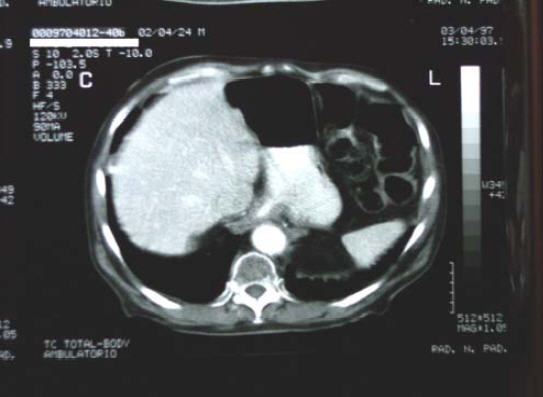

4/4/1995 – TAC

3/4/97 - TAC di controllo evidenzia una: “complessiva riduzione dell’ispessimento al 3° distale esofageo:

“… l’esame TC del torace e dell’addome eseguito prima e dopo per

fusione e.v. di mdc iodato, con tecnica di acquisizione volumetrica, ha

mostrato una complessiva riduzione dell’irregolare ispessimento del

tessuto periesofageo al 3° distale, in sede sovra e sottocardiale, con

interessamento del fondo gastrico. L’area di interesse mostra subire un

evidente enhancement alla perfusione del mdc iodato…”.